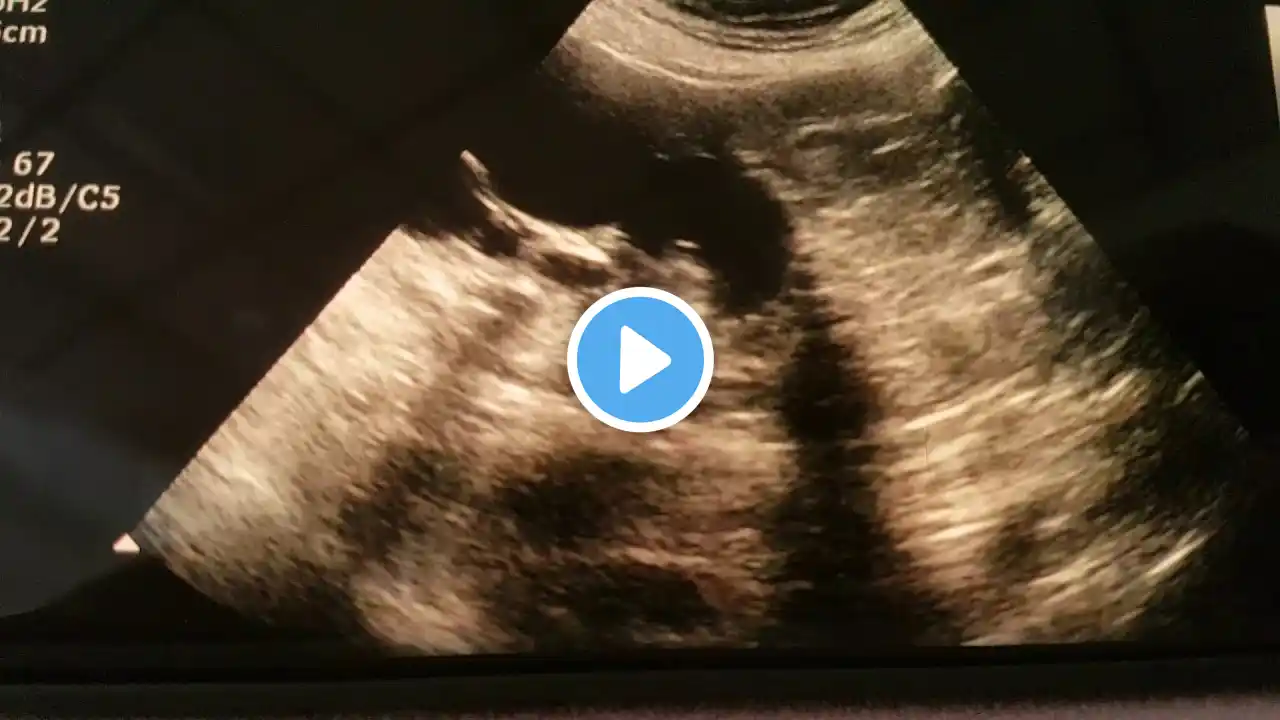

BILATERAL OBSTRUCTIVE UROPATHY due to HYPERTROPHIED TRABECULAE of UB wall

by DR TAHIR A SIDDIQUI ( consultant sonologist ) Gujranwala. Pakistan